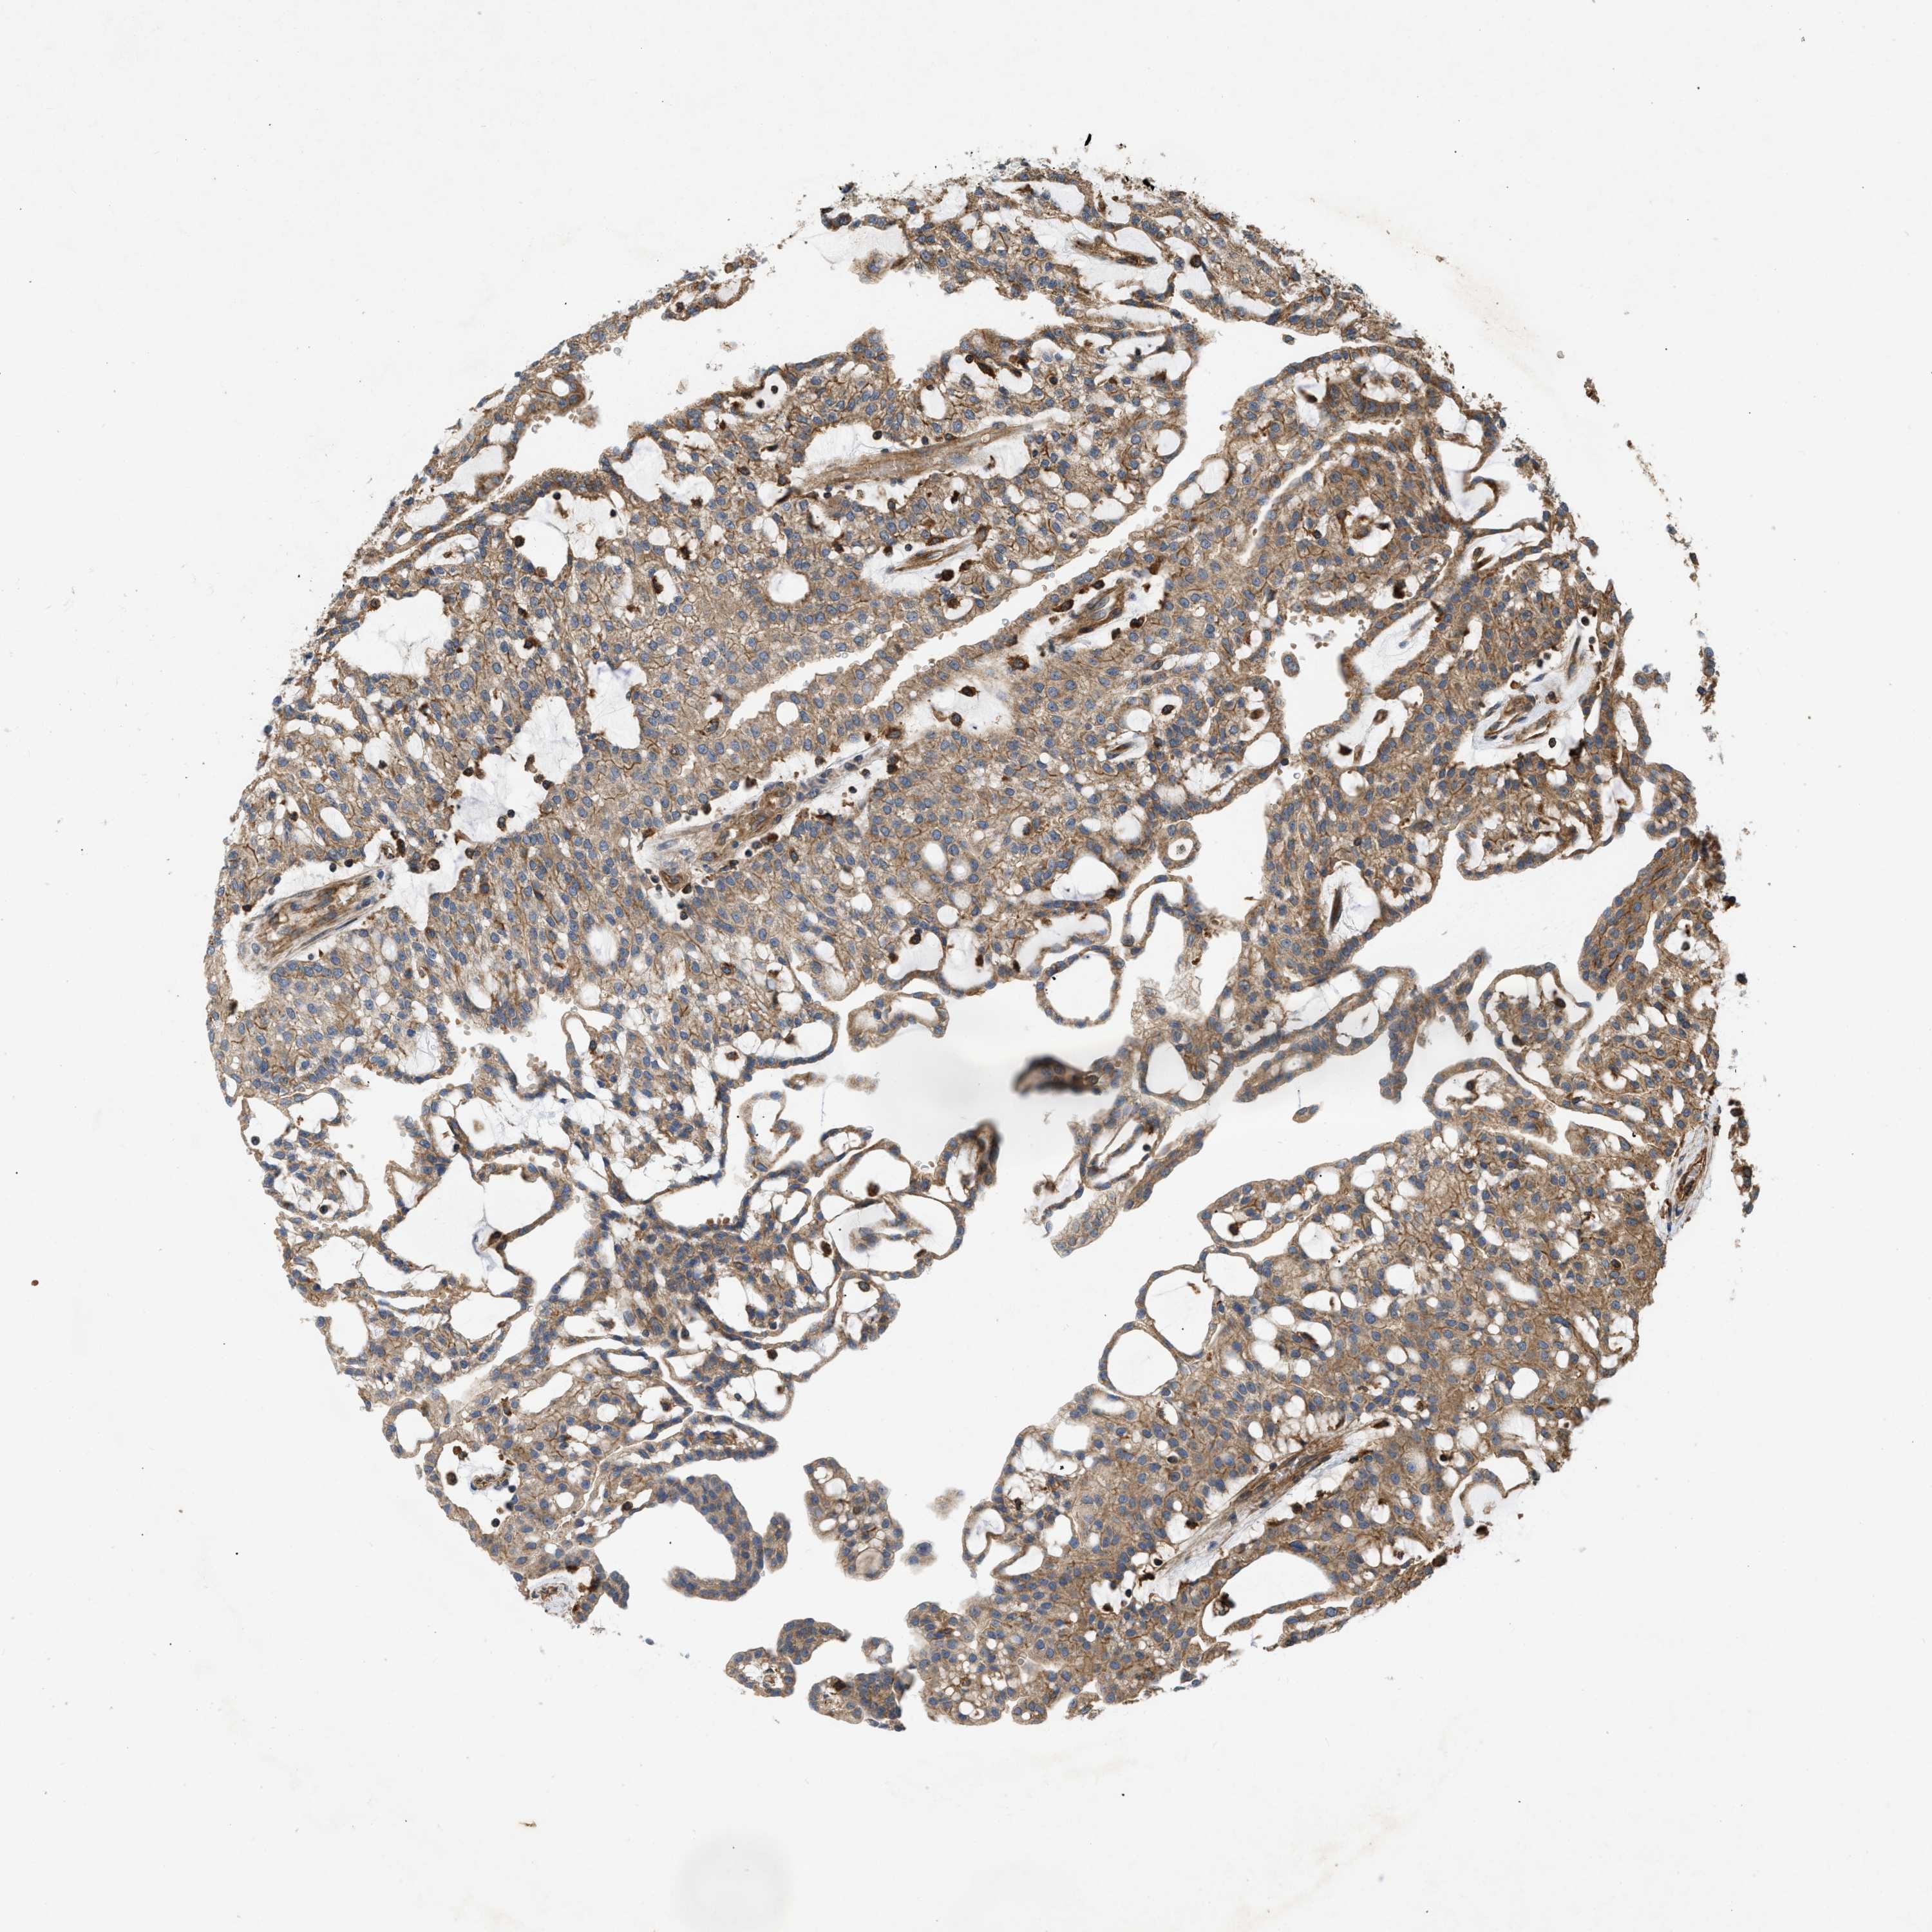

KIDNEY RENAL CLEAR CELL CARCINOMA (VALIDATION) - Interactive survival scatter ploti

The Survival Scatter plot shows the clinical status (i.e. dead or alive) for all individuals in the patient cohort, based on the same data that underlies the corresponding Kaplan-Meier plots. Patients that are alive at last time for follow-up are shown in blue and patients who have died during the study are shown in red.

The x-axis shows the expression levels (FPKM) of the investigated gene in the tumor tissue at the time of diagnosis. The y-axis shows the follow-up time after diagnosis (years). Both axes are complimented with kernel density curves demonstrating the data density over the axes. The top density plot shows the expression levels (FPKM) distribution among dead (red) and alive patients (blue). The right density plot shows the data density of the survived years of dead patients with high and low expression levels respectively, stratified using the cutoff indicated by the vertical dashed line through the Survival Scatter plot. This cutoff is automatically defined based on the FPKM cutoff that minimizes the p-score. The cutoff can be changed by dragging the vertical line or by entering a cutoff value in the square labeled "Current cut-off".

Under the Survival Scatter plot the p-score landscape (black curve; left axis) is shown together with dead median separation (red curve; right axis). Dead median separation is the difference in median mRNA expression between patients who have died with high and low expression, respectively. It is calculated as follows: median FPKM expression of dead patients with high expression - median FPKM expression of dead patients with low expression. This is intended to aid the user in visually exploring custom cutoffs and the associated p-scores and dead median separation.

Individual patient data is displayed and can be filtered by clicking on one or more of the category buttons on the top of the page. Categories describing expression level and patient information include: high, low, alive, dead, female, male and tumor stages. The scale of the x-axis can be toggled between linear and log-scale by clicking on the "x log" button. Mouse-over function shows TCGA ID, patient information and mRNA expression (FPKM) for each patient.

& Survival analysisi

Kaplan-Meier plots summarize results from analysis of correlation between mRNA expression level and patient survival. Patients were divided based on level of expression into one of the two groups "low" (under cut off) or "high" (over cut off). X-axis shows time for survival (years) and y-axis shows the probability of survival, where 1.0 corresponds to 100 percent.

GNB4 is not prognostic in Kidney Renal Clear Cell Carcinoma (validation)

Best expression cut offi

Based on the FPKM value of each gene, patients were classified into two groups and association between prognosis (survival) and gene expression (FPKM) was examined. The best expression cut-off refers the FPKM value that yields maximal difference with regard to survival between the two groups at the lowest log-rank P-value. Best expression cut-off was selected based on survival analysis .

When clicking on this number, the vertical dashed line indicating cut-off, the interactive survival plot, and the Kaplan-Meier curve will be adjusted to show results based on the best expression cut-off.

: 16.77

TCGA RNA samplesi

RNA-seq data is reported as average FPKM (number Fragments Per Kilobase of exon per Million reads), generated by the The Cancer Genome Atlas (TCGA) .

Normal distribution across the dataset is visualized with box plots, shown as median and 25th and 75th percentiles. Points are displayed as outliers if they are above or below 1.5 times the interquartile range. FPKM values of the individual samples are presented next to the box plot.

Average pTPM 21.0

Number of samples 100